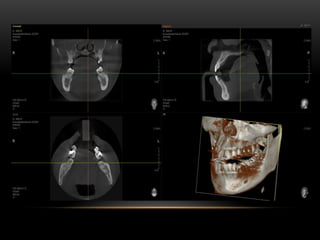

TOMOGRAFIA DA BOCA ( DENTES)

FAN BEAN ECONE BEAN • • A TC é classificada de acordo com o formato do feixe de raios X utilizado: tomografia computadorizada de feixe em leque (Tomografia Computadorizada Fan Beam) e tomografia computadorizada volumétrica de feixe cônico (Tomografia Computadorizada Cone Beam), que é a que utilizamos na Odontologia.

A técnica CONEBEAM faz uma varredura, com uma única rotação de uma fonte de raios X. Um pistão sensor de raios X, fixo por um braço, gira em torno da cabeça do paciente de forma a adquirir muitas projeções simples ou base de imagens. Ou seja: em uma exposição única com o uso de um feixe em forma de cone, rotacionando em 360 graus, obtém-se uma imagem tridimensional do paciente na tela do computador, imagem que pode ser trabalhada, segmentada e analisada em qualquer plano ou incidência.